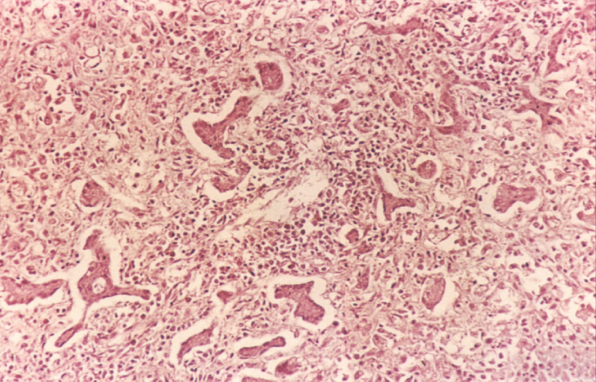

(2)亚急性重型肝炎:多数是由急性重型肝炎迁延而来或一开始病变就比较缓和呈亚急性经过。少数病例可能由普通型肝炎恶化而来。本型病程可达一至数月。病变特点是既有大片的肝细胞坏死,又有肝细胞结节状再生。由于坏死区网状纤维支架塌陷和胶原纤维化,致使再生的肝细胞失去原有的依托呈不规则的结节状,失去原有小叶的结构和功能。小叶内外有明显的炎细胞浸润。小叶周边部小胆管增生并可有胆汁淤积形成胆栓。肉眼观,肝不同程度缩小,被膜皱隔,呈黄绿色(亚急性黄*色肝萎缩)。病程长者可形成大小不等的结节,质地略硬。切面黄绿色(胆汁淤积),交错可见坏死区及小岛屿状再生结节。此型肝炎如及时治疗有停止进展和治愈的可能。病程迁延较长(如1年)者,则逐渐过渡为坏死后性肝硬化。病情进展者可发生肝功能不全。